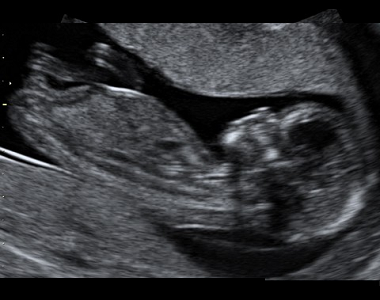

Screening v 1.trimestru

Ahoj bolky :)Tak jsme teď v pondělí byli na 1. velkém UTZ bylo to něco úžasnýho a nezapomenutelnýho!!! Viděli jsme toho našeho andílka snad ze všech stran, pan doktor nám vše vysvětloval, slyšeli jsme...

Diskuze 3